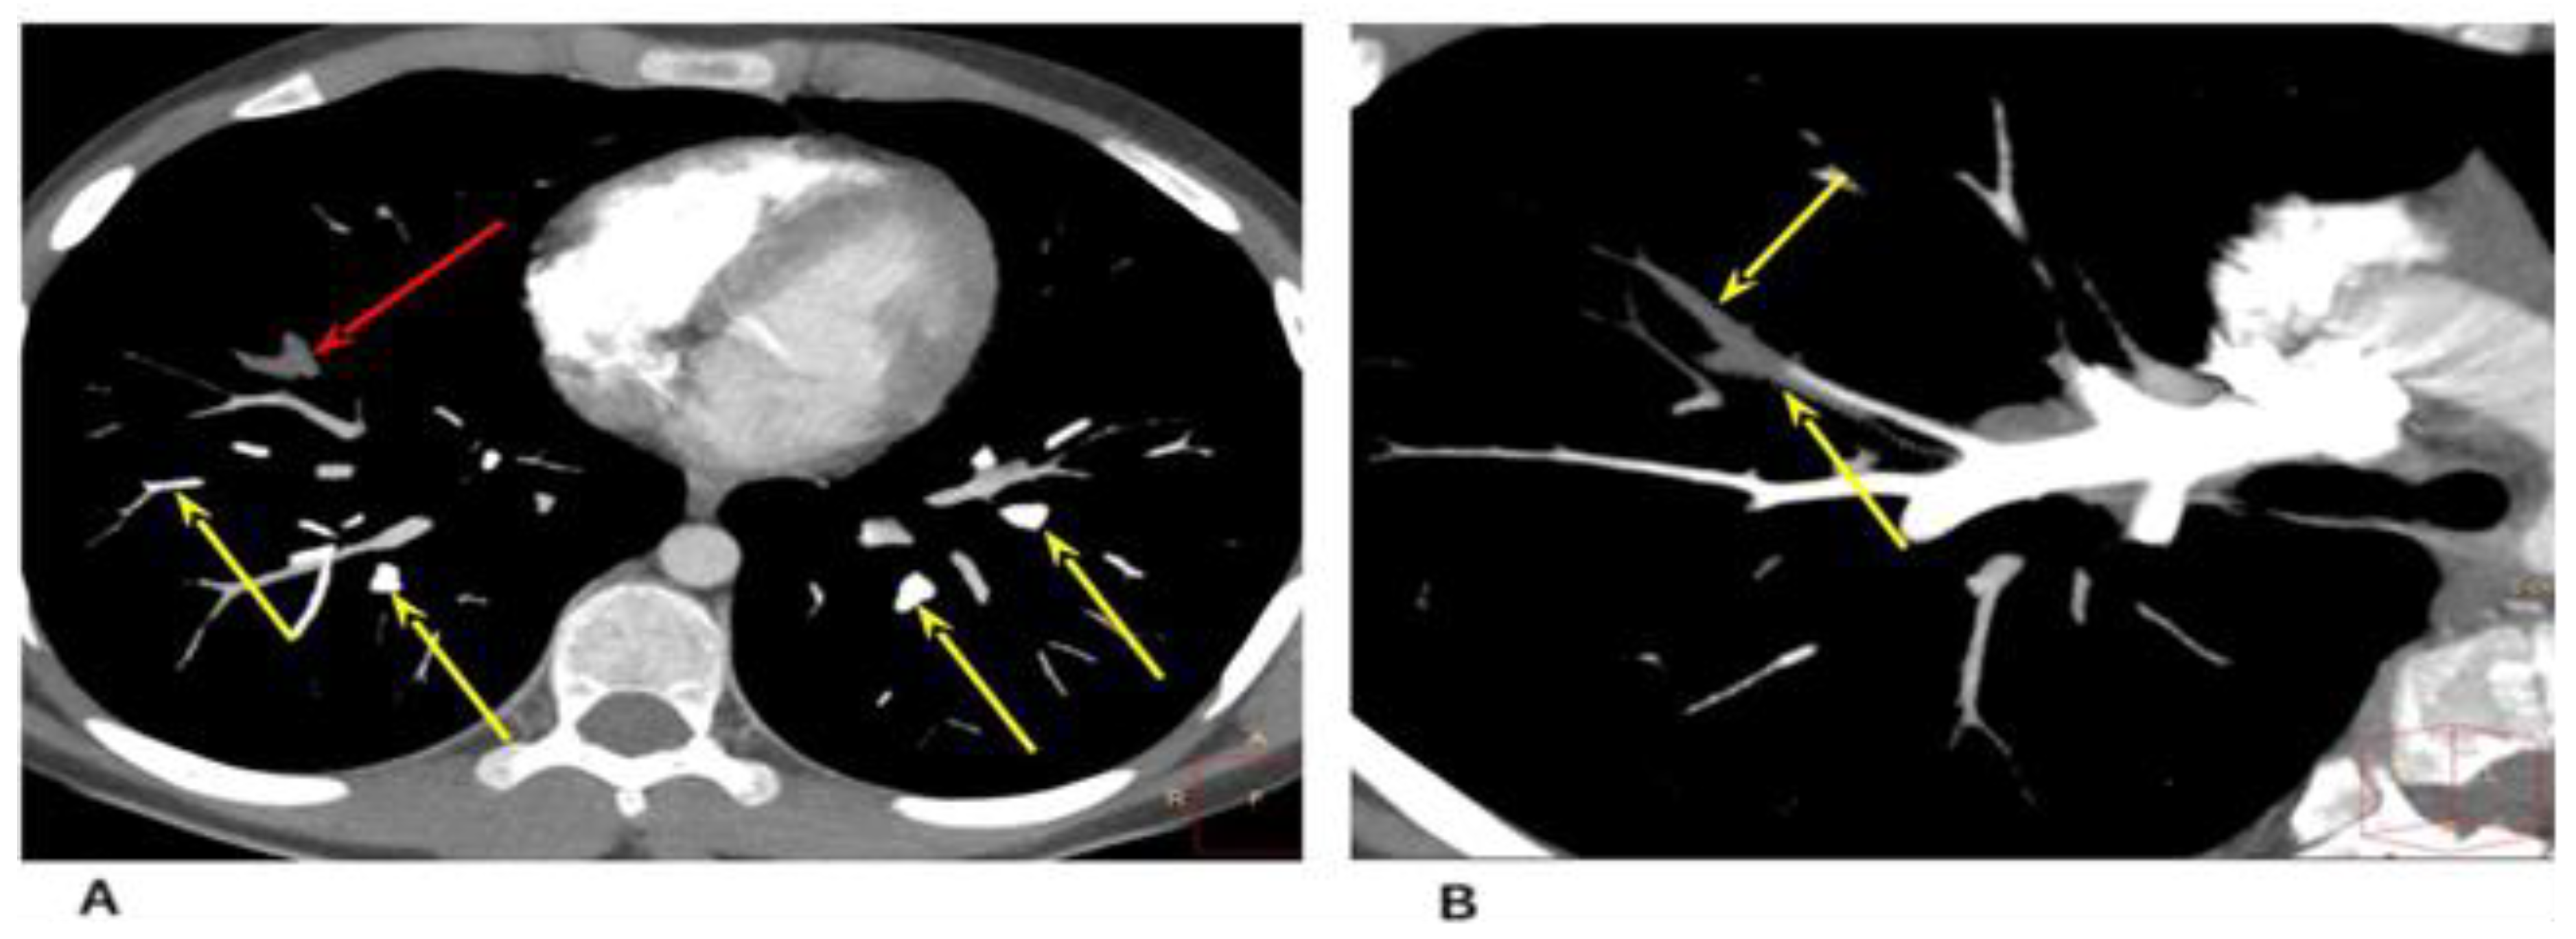

2. Case 1

2.1. Examination Data

2.2. Substantiation of Diagnosis

3. Case 2